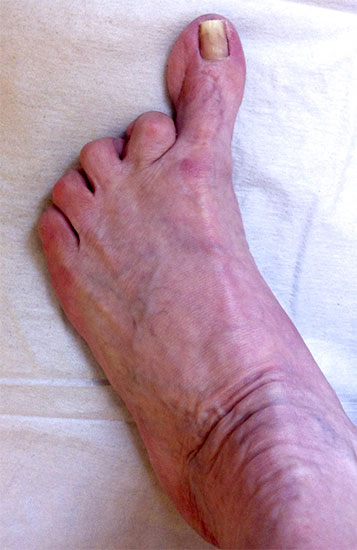

11"> Der Hallux varus Winkel  <a class=11" title="Der Hallux varus Winkel 11" srcset="/assets/images/2/4-vk3bypbg5s5x7zc.jpg 1x, /assets/images/3/4-aax2sd1hrpnrvrb.jpg 1.452x" width="270" height="240" loading="lazy">

Abbildung 3

Die bildgebende Diagnostik hilft bei der Klärung der Ätiologie und des Ausmaßes der Fehlstellung. Hierzu sind Röntgen­aufnahmen im Stand in mindestens zwei Ebenen unter Belastung des Fußes erforderlich. Mit Hilfe der belasteten Röntgenaufnahmen wird der Hallux-varus-Winkel, d. h. den Winkel zwischen der Achse der Grundphalanx der Großzehe und der Achse des ersten Mittelfußknochens bestimmt, sowie etwaige Rotationsfehlstellungen des 1. Strahls verifiziert. Eventuelle knöcherne Fehlanlagen bei kongenitalen Deformitäten können hierdurch ebenfalls verifiziert werden.

Weitere Beurteilungskriterien sind:

• degenerative Veränderungen des MTP I

• Kongruenz des MTP I- Gelenkes

• Form und Stellung des Mittelfußköpfchens I

• Ausprägung der Pseudoexostose.

• PASA-Winkel, d. h. der periphere Artikulationswinkel des Großzehengrundgelenkes.

Zur Klärung der Ätiologie wird der intermetatarsale Winkel zwischen Os metatarsale I und II bestimmt. Ist dieser kleiner als 5° oder gar negativ, ist eine Varusstellung der Großzehe oft die Folge.

Am Röntgenbild des belasteten Fußes bestimmt man die Lage der Sesambeine zum 1. Mittelfußköpfchen.

Anhand der Röntgenaufnahme lassen sich die Folgen einer eventuellen Voroperation bestimmen, wie z. B. die Stellung des ersten Mittelfußköpfchens, des ersten Metatarsale nach Korrekturen der Achse bei einer Hallux-valgus-Operation. Mitunter bestehen Nekrosen des Mittelfußköpfchens oder eine übermässige Resektionen der Pseudoexostose. Auch die Länge des 1. Metatarsale kann von Interesse sein, z. B. nach einer Lapidusarthrodese (Johnson 1994).